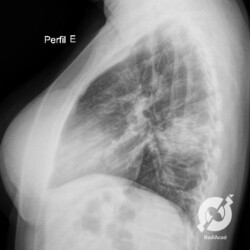

Os agentes etiológicos infecciosos são variados (bactérias, vírus, fungos, parasitas…), mas o que ocorre nos pulmões durante uma infecção por qualquer tipo de agente é a substituição do ar alveolar por secreção (pus, muco, eventualmente sangue ou necrose…) e com isso a manifestação radiográfica vai ser a mesma já que todas estas secreções apresentam a mesma densidade radiográfica: partes moles.

E o nome dado a esta alteração radiográfica que corresponde à substituição do ar alveolar por líquido é a consolidação alveolar.

Uma consolidação alveolar é, por definição, uma opacidade (imagem densa, branquinha) homogênea ou às vezes heterogênea (pela presença de calcificações ou cavidades), de limites mal definidos, exceto quando toca a pleura da parede ou das cissuras pulmonares. É um termo usado tanto em radiografia, como em tomografia computadorizada. Na tomografia, um outro termo é usado: vidro fosco, que é uma opacidade (branquinha mas não tanto como a consolidação), que borra o pulmão mas deixa ver os vasos de permeio (igual bigode de adolescente: dá pra ver todo o fundo).

Nós vamos mostrar aqui um pequeno apanhado de pneumonias de variados agentes, em diversos segmentos e lobos pulmonares, com extensões variadas. O objetivo é identificar o padrão radiológico de consolidação alveolar e não determinar o agente infeccioso, isso vai ser assunto para mais adiante. Aliás já antecipo que é fundamental saber localizar a lesão, porque alguns destes bichos gostam de determinados segmentos, alguns tumores também têm as suas preferências, então localização é fundamental. Se localização não fosse importante, um apartamento na beira do mar sairia o mesmo preço de um apartamento de frente pra BR-101, concordam?